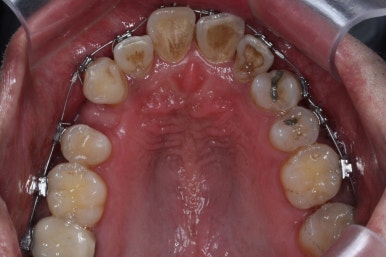

부산치아교정 키다리아저씨치과에 처음 내원 당시의 입안 모습입니다.

여러 가지 문제점이 있는데 하나씩 살펴볼게요.

치열이 많이 삐뚤하네요.

많이 삐뚠 상태에서 장기간 사용하다 보면 안좋은 방향으로 치아가 힘을 받게 되고 마모나 치아 목부분 패임이 심해집니다.

양치가 힘들어요. 양치가 힘들다 보니 세게 닦게 되고 치아 손상은 더 심해져요. 25세의 나이였는데 나이에 비해서 치아나이가 굉장히 많은거죠.

화살표 부분에 원래 송곳니가 있어야 되는데 보이질 않네요. 결손치아일 수도 있고 매복치아일 수도 있겠어요.

왼쪽 위 어금니도 한 개가 없어서 빈공간이 약간 남아있어요.